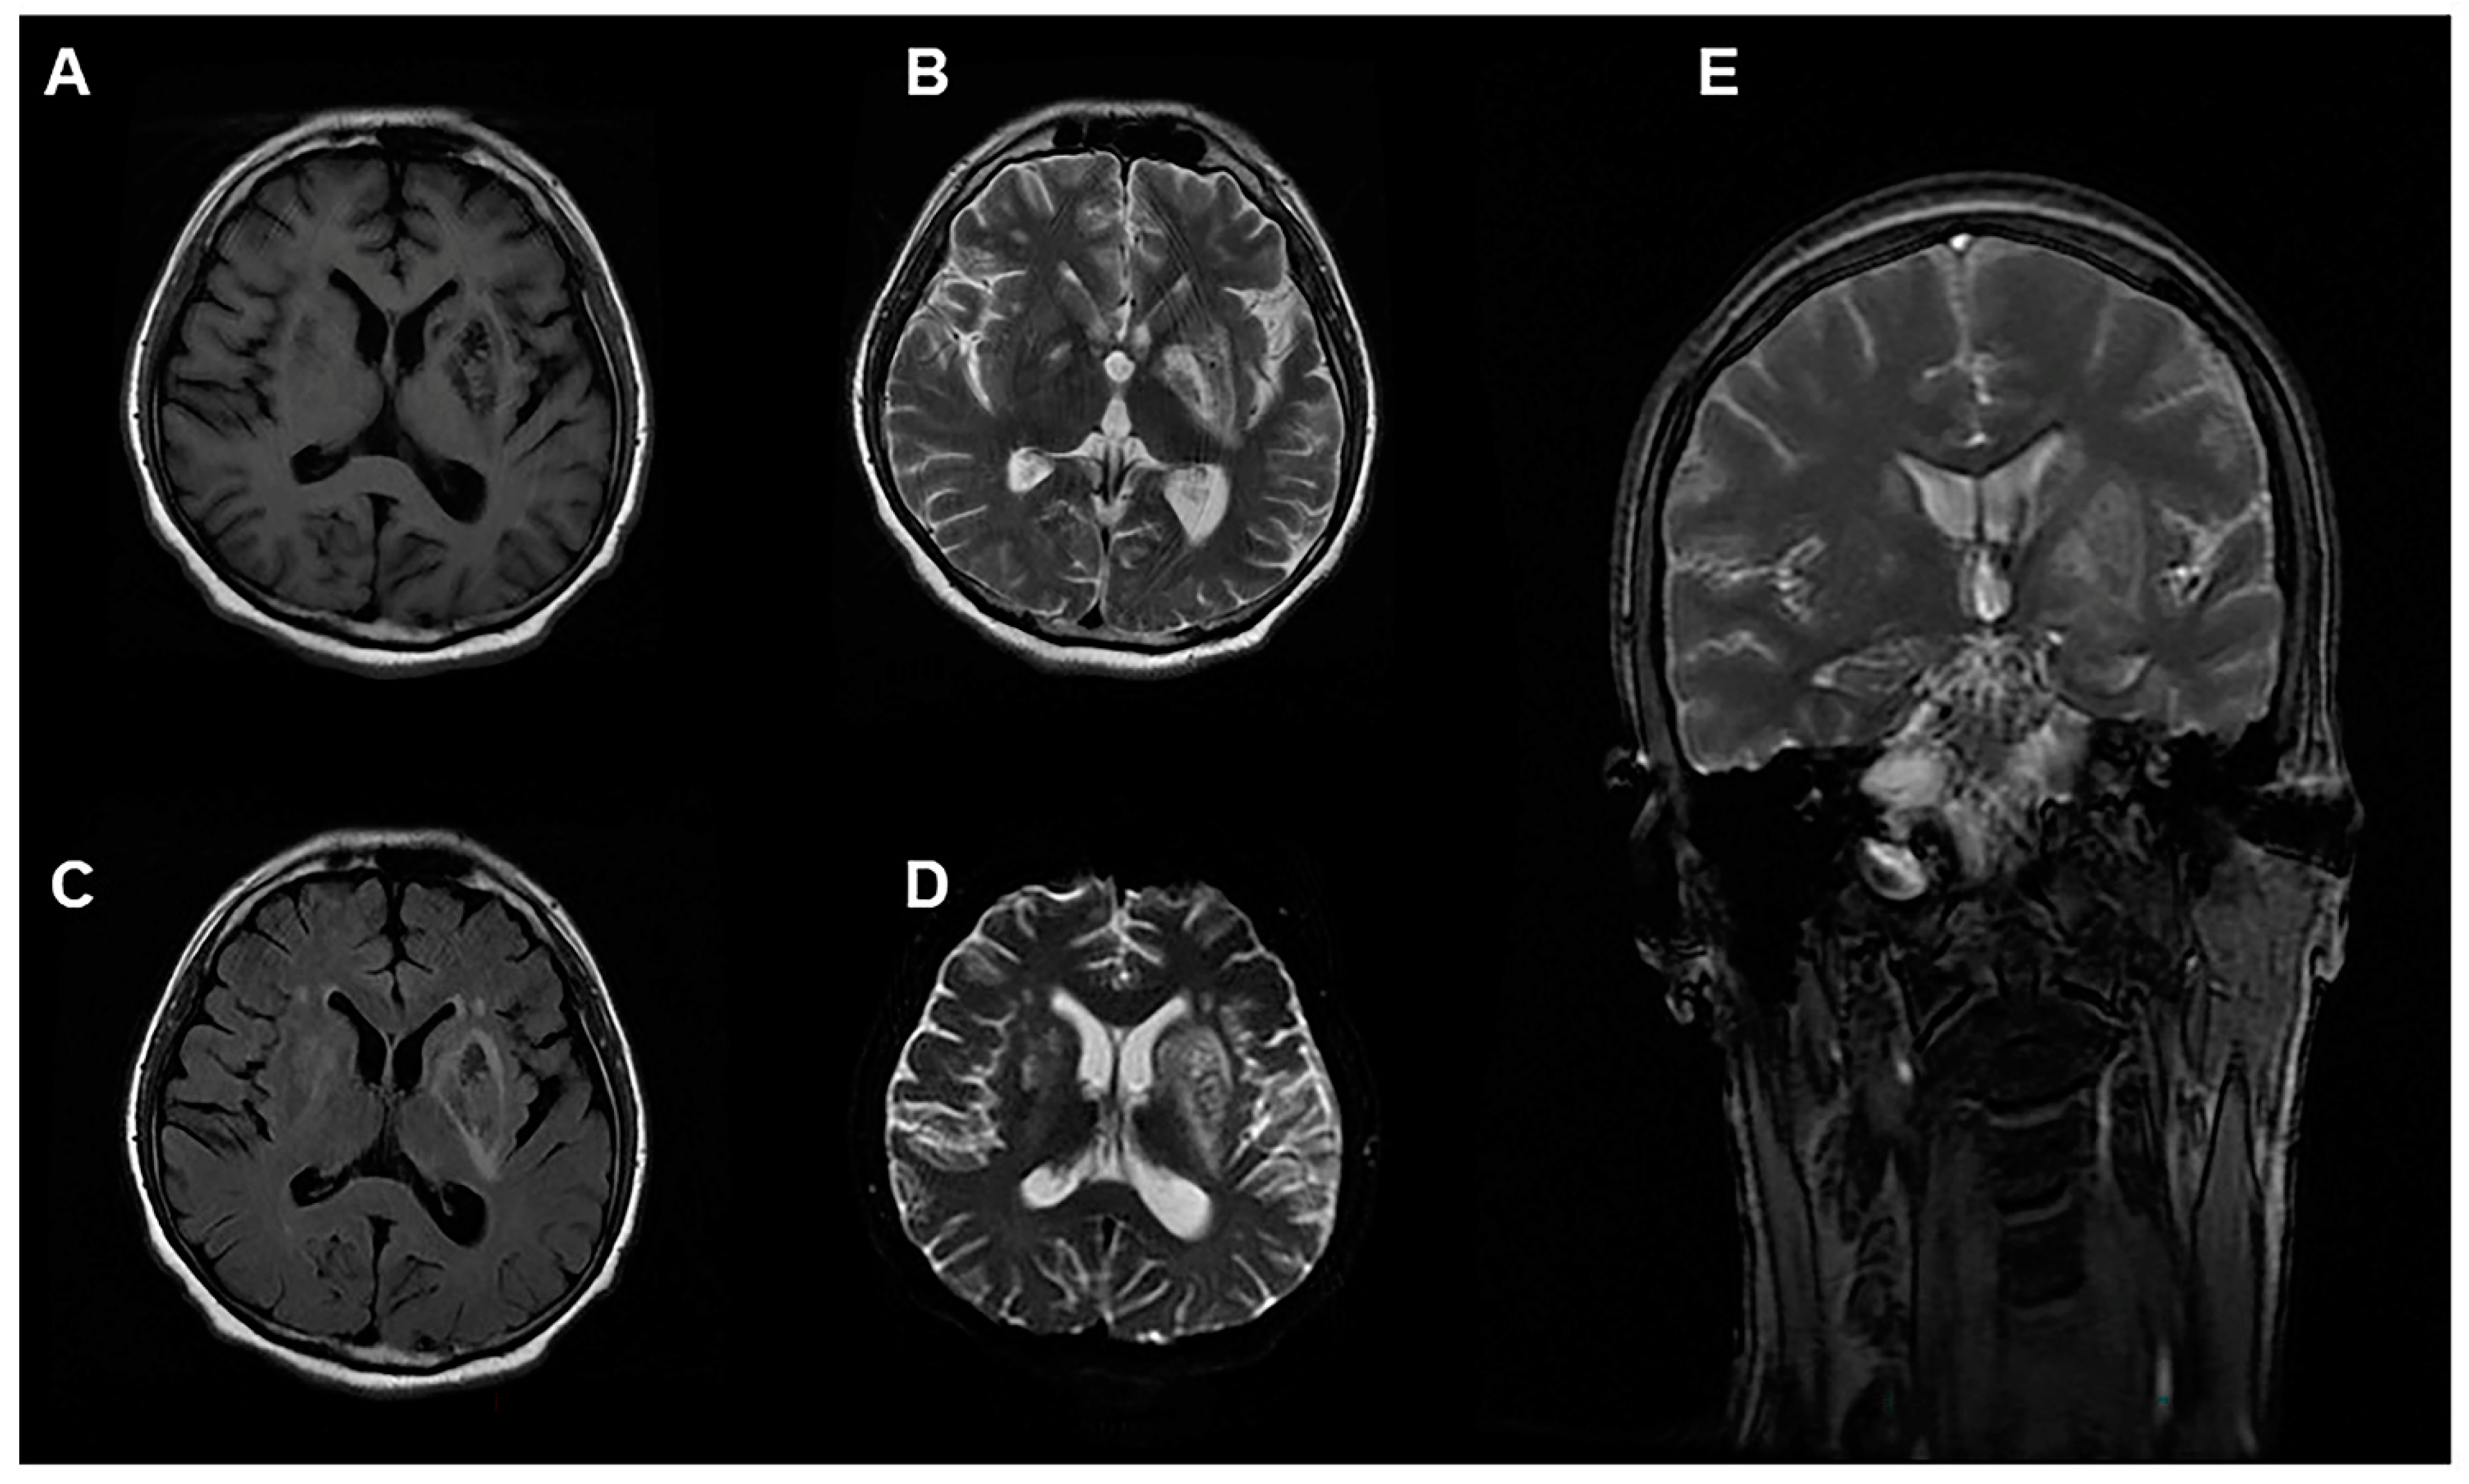

During the course of treatment, the patient’s urine output increased. On the 19th day of onset, the patient’s urine output reached 2000 mL/day. However, at this time, his cognitive function declined, language comprehension and calculation ability declined, recent memory recall also decreased and he experienced mild disorientation, with a MMSE score of 19 and a Montreal cognitive assessment (MoCA) score of 15. The muscle strength of his appendages was graded at 5, with normal muscle tone and unremarkable tendon reflex and neck resistance, and a negative Babinski sign. Magnetic resonance imaging of the head revealed abnormal signals in the bilateral basal ganglia and corona radiata, and the patient was diagnosed with toxic encephalopathy. The lesion showed hypointense-to-isointense signal on T1-weighted images, and hyperintense signal on T2-weighted-images. Diffusion-weighted imaging (DWI), apparent diffusion coefficient (ADC) mapping and fluid-attenuated inversion-recovery (FLAIR) sequencing also demonstrated heterogeneous high signal (Figure 2).

Figure 2.

Images of a 35-year-old man exposed to 5-amino-2-(trifluoromethyl)pyridine. MRI 20 days after exposure showing abnormal signal intensity on (A) T1WI, (B) T2WI, (C) T2 FLAIR, (D) DWI and (E) T2WI of coronal in the bilateral cerebral hemispheres. T1WI, T1-weighted image; T2WI, T2-weighted image; DWI, diffusion-weighted imaging; FLAIR, fluid-attenuated inversion-recovery sequency.

On the 19th day of onset, the patient developed cognitive decline. MRI showed symmetrical hypointense signal on T1WI in the basal ganglia and corona radiata, and high signal on T2WI and DWI. The clinical and MRI findings were similar to those of delayed encephalopathy after acute carbon monoxide poisoning; however, the MRI findings are also similar to those of toxic encephalopathy caused by organic solvents including extensive white matter density reduction, symmetrical distribution, and no placeholder effect [14,15]. The chemical structure of 5-amino-2-(trifluoromethyl)pyridine is similar to aniline, which can cause neurological damage. However, the patient was comatose and experienced hypoxia for up to 10 h, and the possibility of delayed encephalopathy due to hypoxia could not be ruled out [16]. However, immediate removal, timely treatment of methemoglobinemia, and hypoxia correction are key to improve the overall patient prognosis, irrespective of the cause of toxic encephalopathy [6,17].